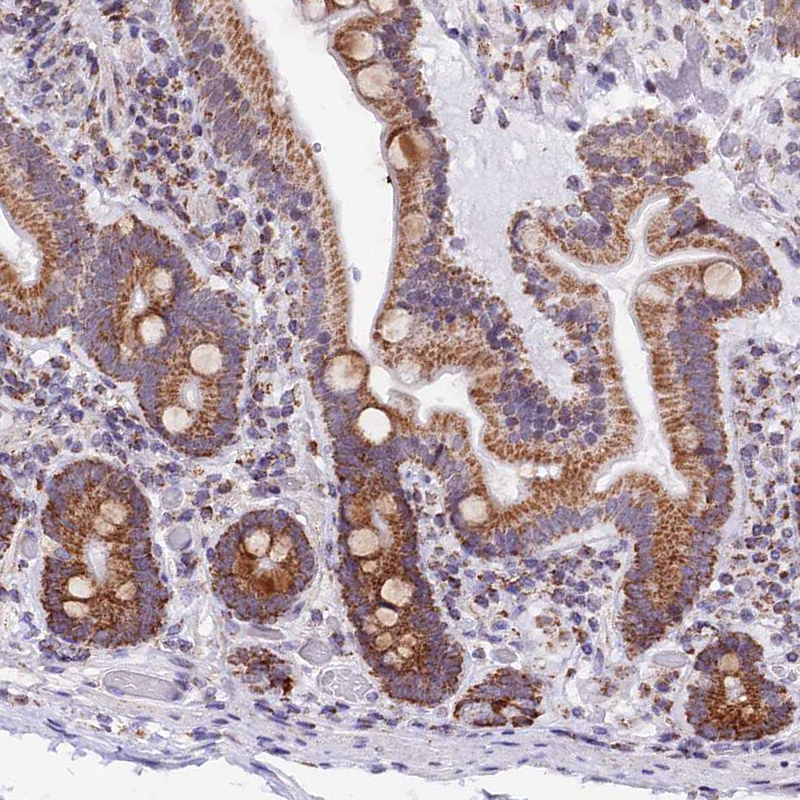

Immunohistochemical staining of human testis shows strong granular cytoplasmic positivity in a subset of cells in seminiferous ducts.